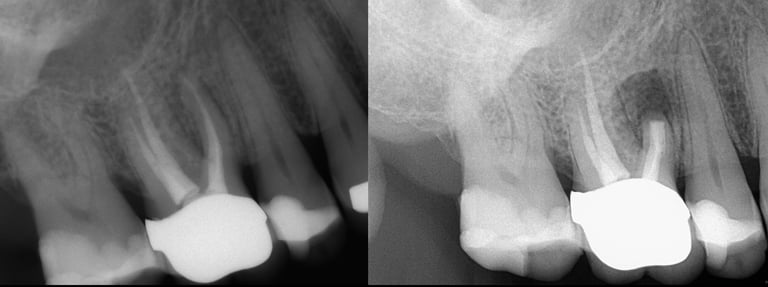

Gallery 4: Healed Cases

Completely healed cases is what matters most. The lesion/infection (black circle) heals in with bone over time.